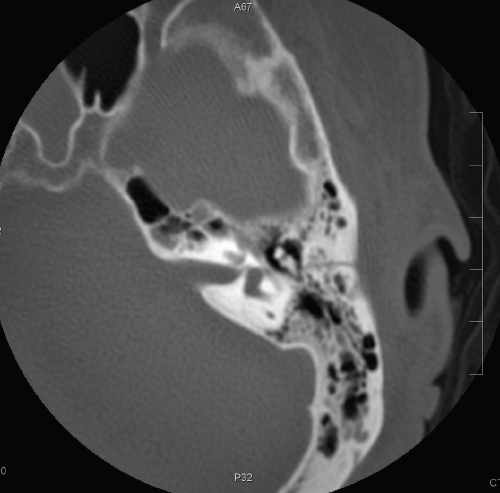

✨Up Next in our Member Spotlight Series - featuring Dr. Rocky Saenz! His passion for education has inspired numerous medical students and radiology residents. Dr. Saenz has made significant strides for DOs and radiologists, enhancing their recognition in the medical field.